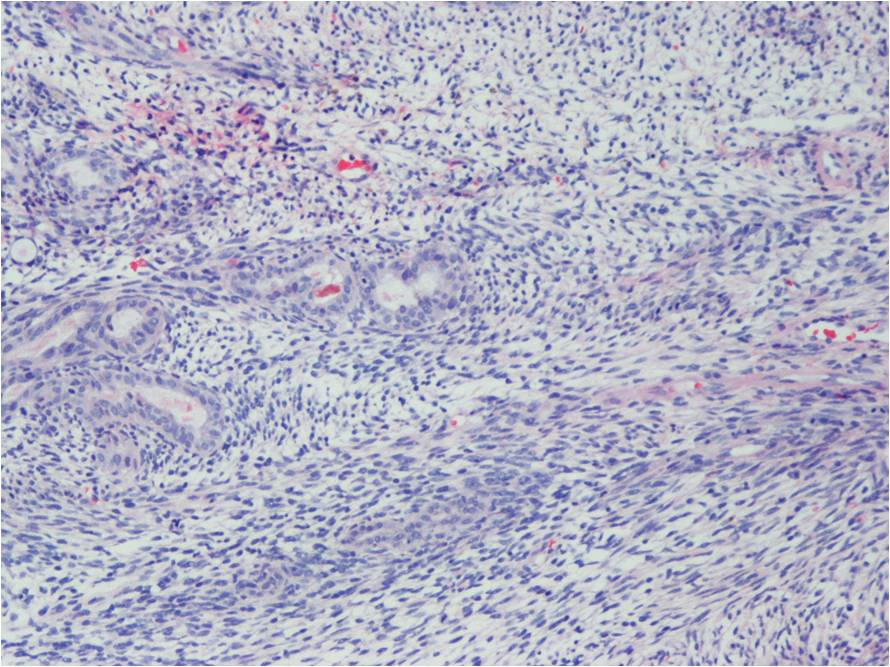

Synovial Sarcoma is composed of two different cell types

Spindle cell (small, uniform, and ovoid cells with pale nuclei and the cytoplasm is sparse)

Epitheloid cell (ovoid nuclei and abundant cytoplasm)

Biphasic form is composed of both epithelial-cell and spindle-cell components in equal proportions (Fig. 6-8)

Monophasic Fibrous type predominantly spindle cell.